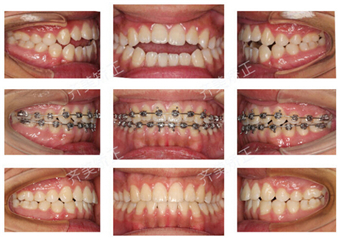

牙齿问题:牙齿错合

治疗周期:1年半多

矫正方式:主流矫正

今天说的这种类型,叫作,我不愿吃面条,我不会嗑瓜子。因为我的前牙没功能。

这就是开合!

当这个孩子说,“我终于可以嗑瓜子了,我之前从来不吃瓜子的,其实它满好吃的。”